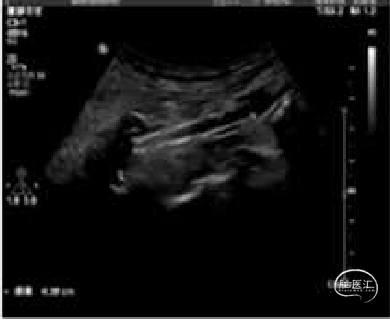

术后复查:

颅脑CT

颈动脉、椎动脉超声:

1、左侧颈总动脉分叉处至颈内动脉近段管腔内可见网状结构强回声(支架);支架长4.4cm;支架近段(位于颈总动脉分叉处)管径5.4mm,流速97cm/s;支架中段(位于颈内动脉球部)管径4.1mm,流速71.9cm/s;支架远段(位于颈内动脉近段)管径4.1mm,流速59.8cm/s。支架中段外侧与管壁间可见大小26.4x3.4mm强回声不均质不规则斑块;支架以远颈内动脉远段流速46.9cm/s,频谱形态正常。

2、双侧椎动脉管径对称,右侧椎间隙管径3.4mm(流速37.3cm/s,RI:0.75);左侧椎间隙管径3.2mm(流速32.1cm/s,RI:0.78)。